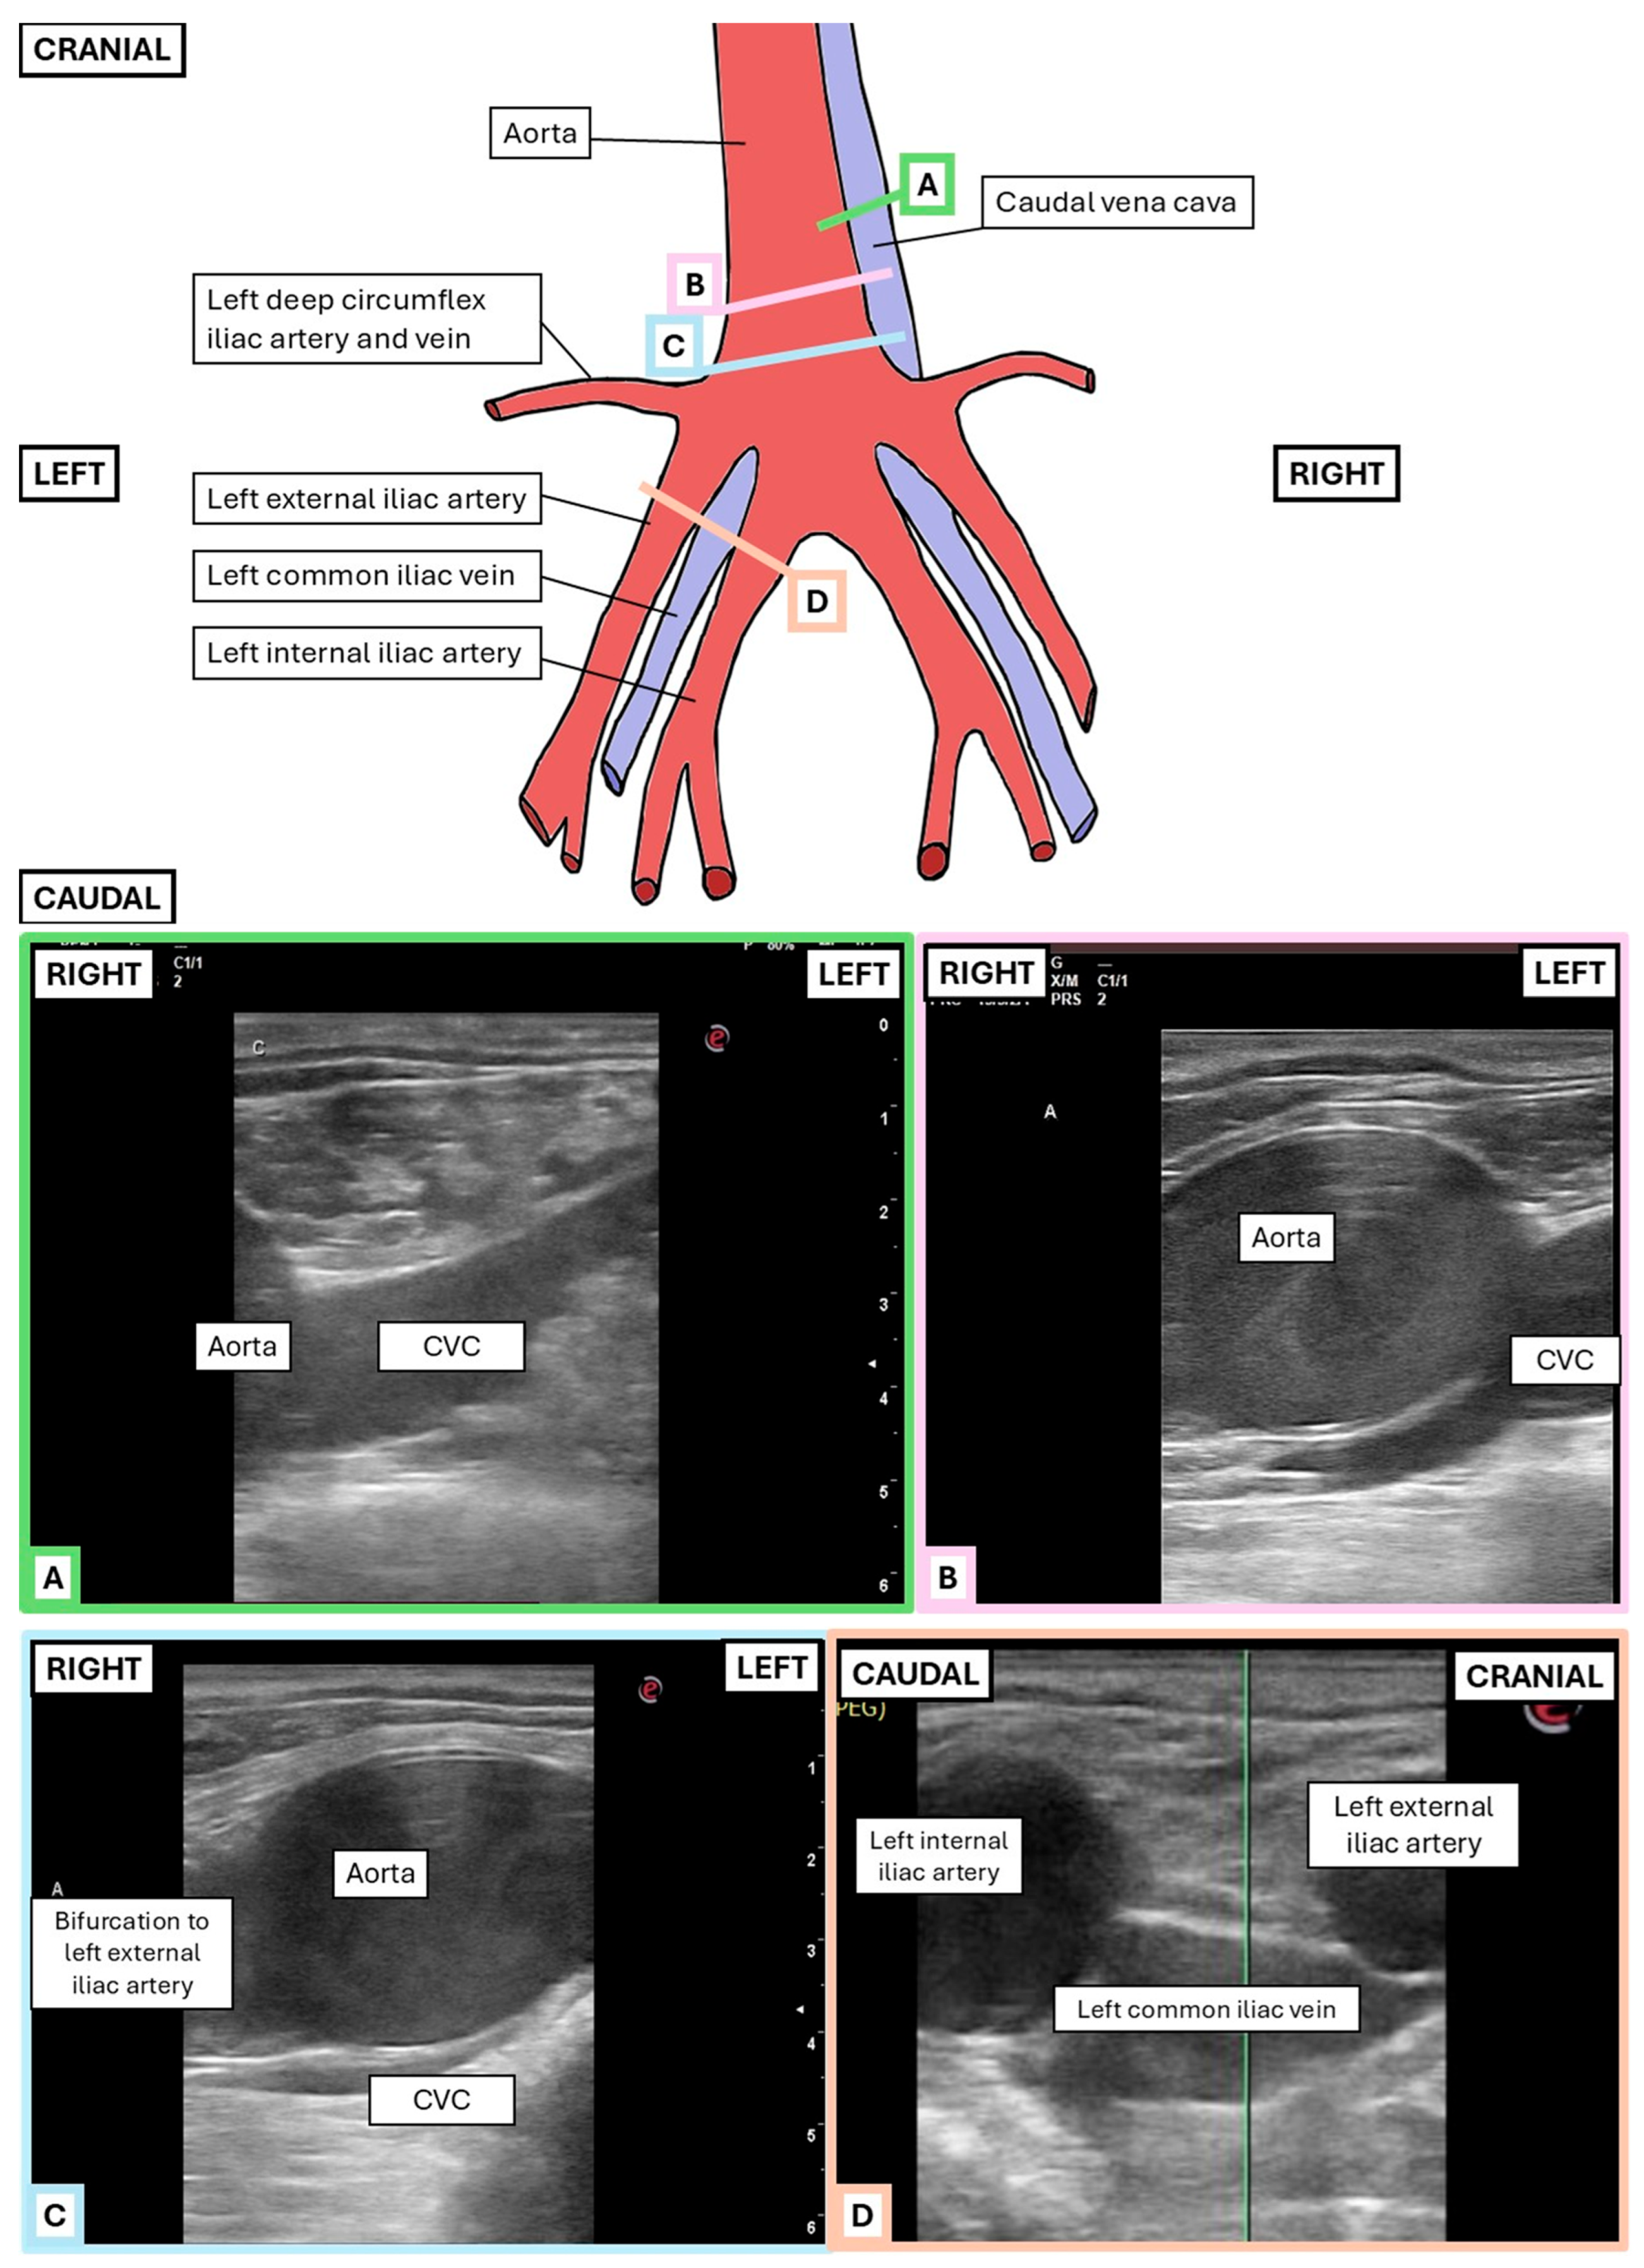

2.2.1. Transrectal Ultrasonographic Technique

2.2.2. Transcutaneous Inguinal Ultrasonographic Technique